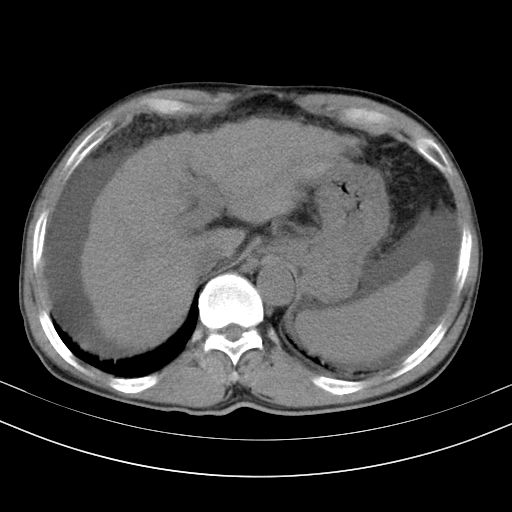

以下是引用随光逐影在2010-2-28 10:23:00的发言:[br]1)考虑肝癌;建议行ct增强扫描检查。2)肝硬化,脾大,腹水。3)慢性胆囊炎。